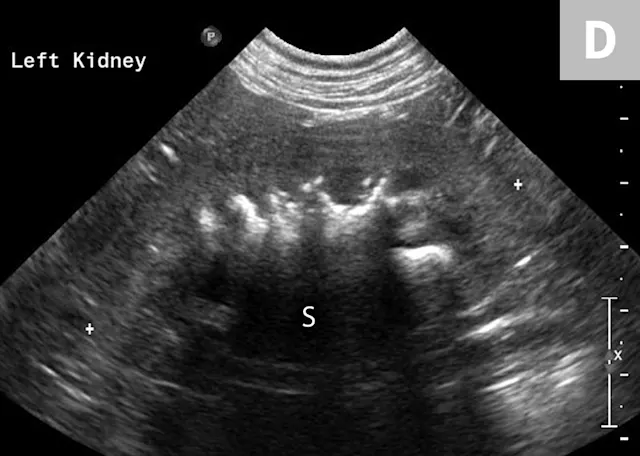

FIGURE 6A

Mild to moderate right hydronephrosis and proximal ureteral dilation in a Dalmatian.